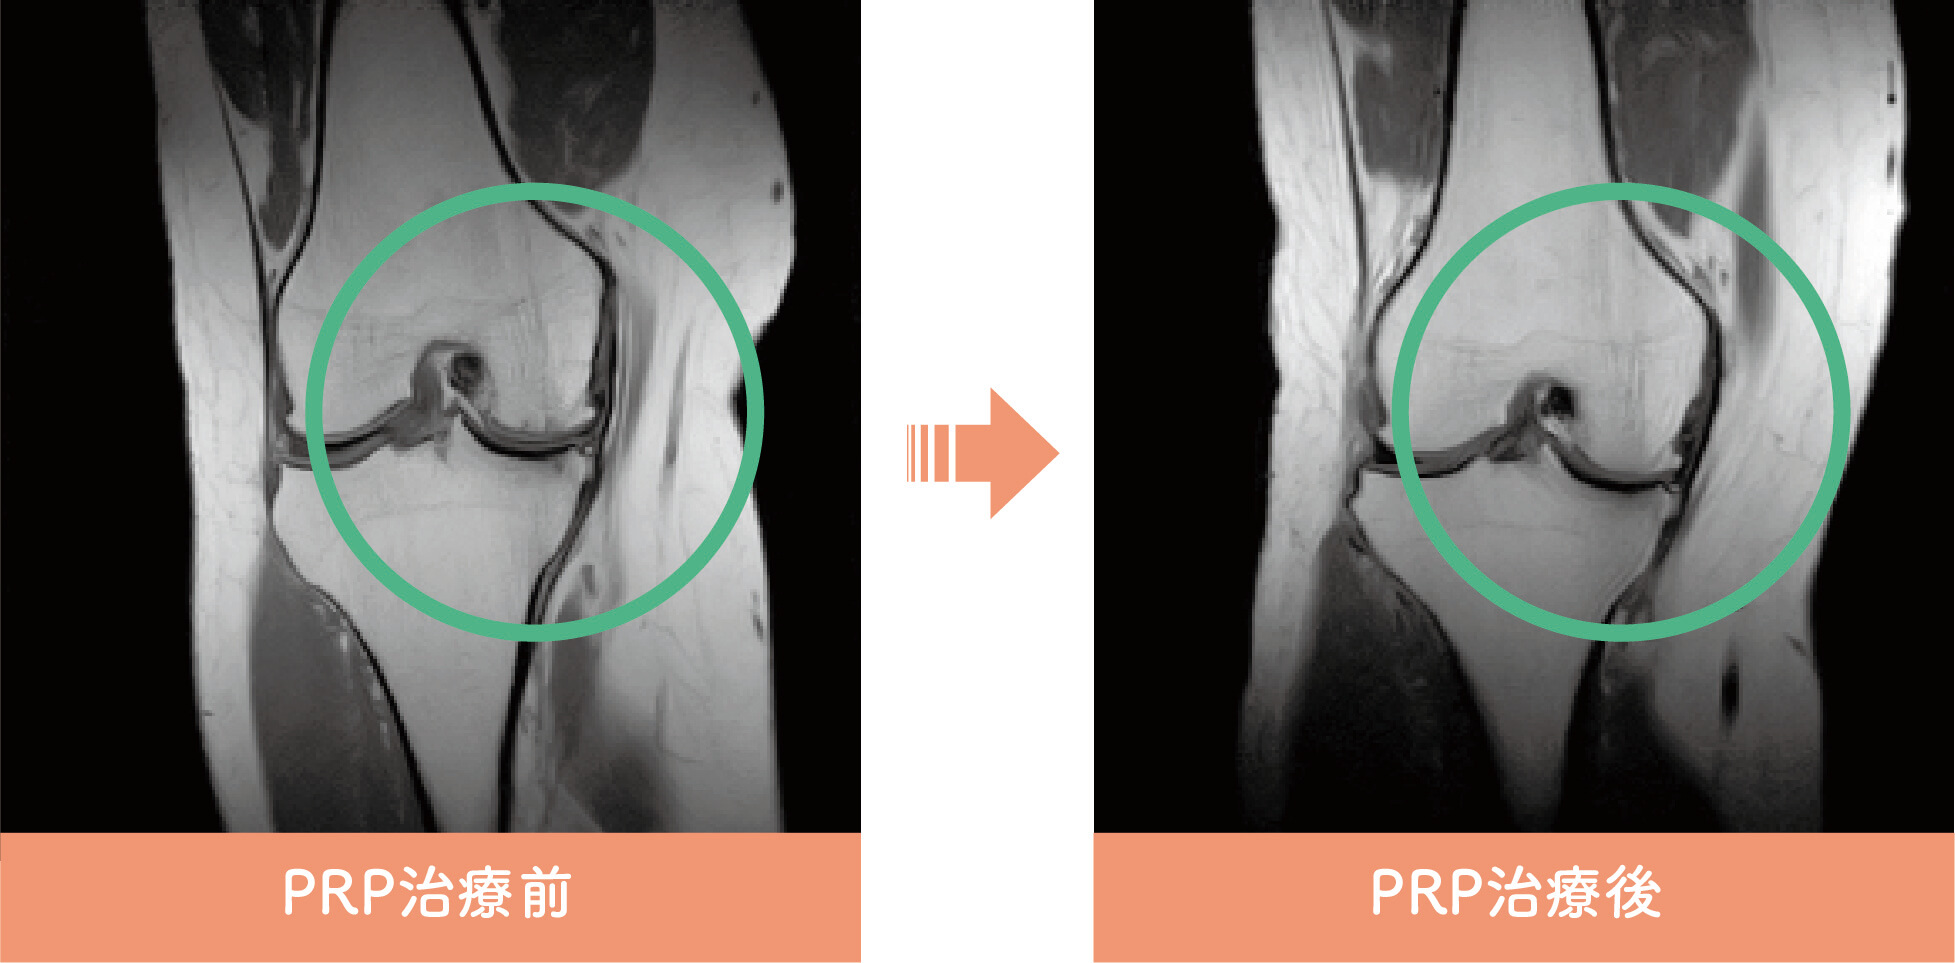

PRP治療前後イメージ